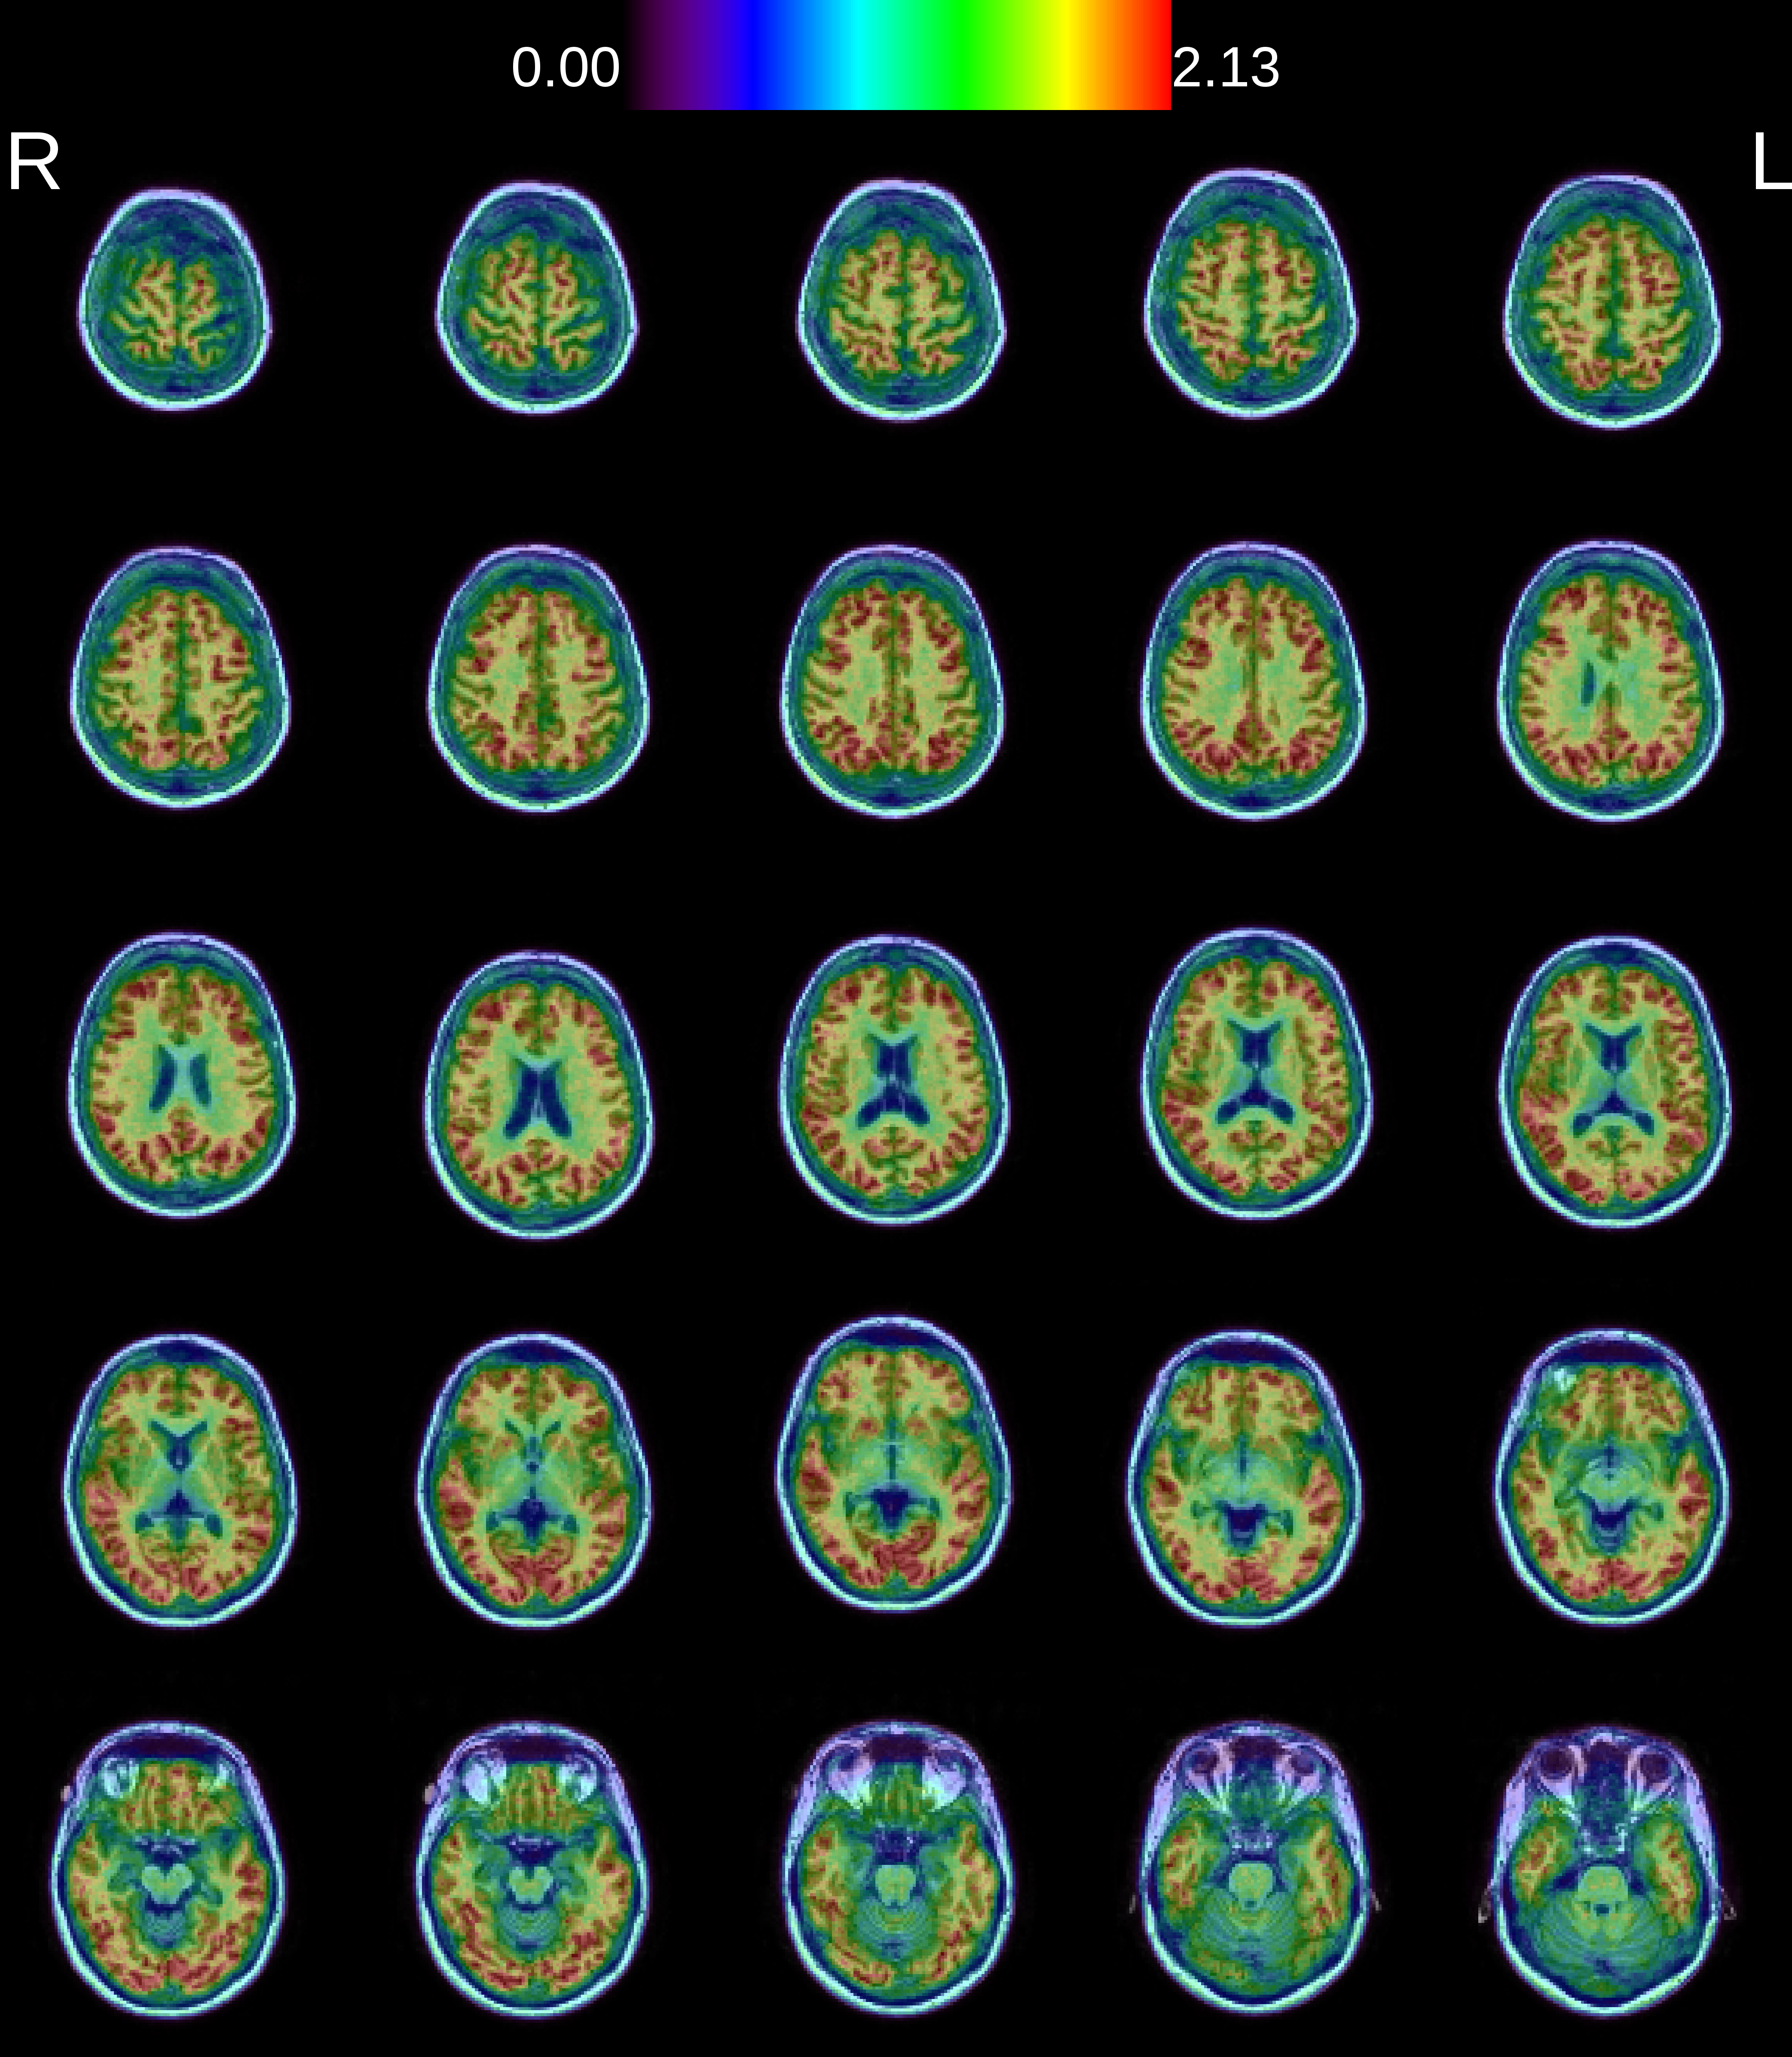

Nuclear imaging toolbox

A toolbox for BrainVISA developed by the |cati_logo| CATI project labs